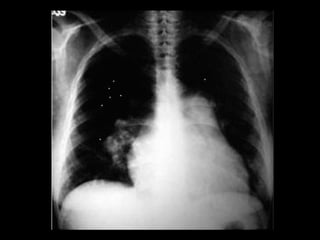

Exames de imagem: Rx Tórax

Primeiro passo na investigação radiológica da

suspeita de HAP;

Achados típicos: aumento do calibre das artérias

centrais, com rápido afilamento dos vasos à medida

que progridem para a periferia;

A área cardíaca pode estar aumentada ou normal;

Calcificação vascular: associado a alta RVP;

Sensibilidade baixa;

Útil para afastar ou sugerir causas de HAP;

Radiografia de tórax normal